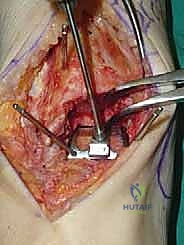

يقوم الدكتور هطيف بعمل شق طولي دقيق في الجزء الأمامي من الكاحل، طوله حوالي 10-15 سم. يتم تشريح الأنسجة بعناية فائقة للوصول إلى المفصل.

* الحماية العصبية الوعائية: هذه هي الخطوة الأكثر حرجاً. يتم تحديد الحزمة الوعائية العصبية (الشريان الظنبوبي الأمامي والعصب الشظوي العميق) وسحبها برفق شديد لحمايتها من أي ضرر جراحي.

3. إزالة النتوءات العظمية وتحضير المفصل (Debridement)

بمجرد كشف المفصل، يقوم الجراح بإزالة الغشاء الزلالي الملتهب والزوائد العظمية (Osteophytes) التي تعيق الحركة. هذه الخطوة ضرورية لاستعادة المعالم التشريحية الطبيعية قبل إجراء القطع العظمي.

4. وضع أدلة القطع (Jig Placement and Alignment)

تعتمد دقة الجراحة على المحاذاة الصحيحة. يتم استخدام أجهزة توجيه متطورة (Jigs) تثبت على عظمة الساق باستخدام دبابيس معدنية. يتم التحقق من صحة الزوايا والمحاور باستخدام جهاز الأشعة السينية المباشر داخل غرفة العمليات (C-arm Fluoroscopy). يضمن الدكتور هطيف أن يكون القطع موازياً للأرض تماماً عند وقوف المريض.